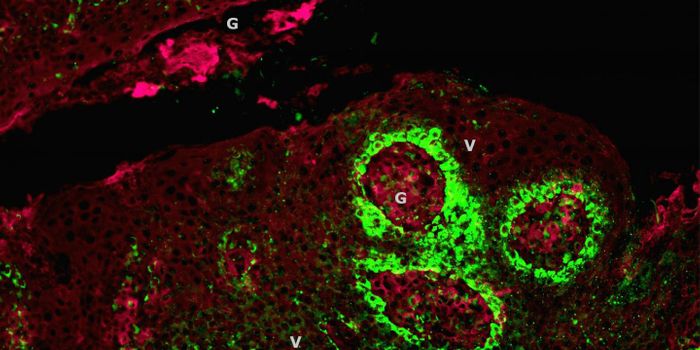

MAR 14, 2016Clinical & Molecular DXJohns Hopkins researchers found a new way to transplant kidney organs from any donor – regardless of compatibility ...